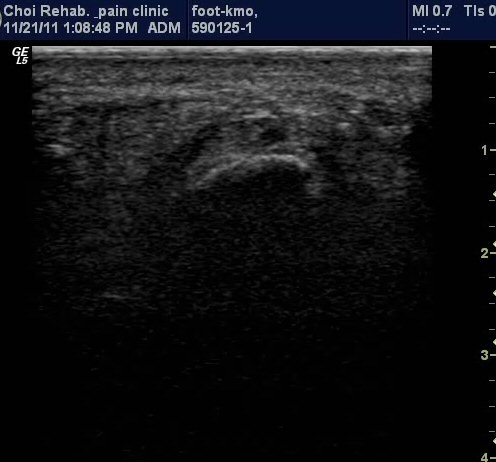

ÃÊÀ½ÆÄ ¼Ò°ß

µÚ²ÞÄ¡ Á¾´Ü¸é°Ë»ç¿¡¼­ Á·Àú±Ù¸·ÀÇ Àú¿¡ÄÚ ºÎÁ¾ÀÌ ¶Ñ·ÈÇÔ(±×¸² 1, 2).

Ⱦ´Ü¸é°Ë»ç¿¡¼­µµ Á·Àú±Ù¸·ÀÇ Àú¿¡ÄÚ ºÎÁ¾ÀÌ ¶Ñ·ÈÇÔ(±×¸² 3).